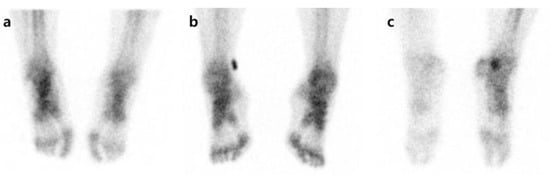

The DITI were performed using an infrared thermography system (T-1000SMART, MESH Co., Ltd., Gangwon-do, Korea). The investigation was carried out in a temperature-controlled room at 19–21 °C. It was conducted after the subject was acclimatized to the room temperature for 15 min without contact and with their shirt removed. From the day before the test, all tests and treatments that can irritate the skin were avoided, and drugs that could affect the sympathetic nervous system were stopped. The degree of infrared emission was expressed in pixels through a computer monitor, and the body surface temperature was expressed visually through a total of 16 color grades (grade 1 to 16). The grade difference between the affected and unaffected sides was calculated (Figure 2). The diagnosis of CRPS through DITI was defined as a difference in one or more color grades in the ROI on the affected and unaffected sides of the image taken from the patients’ front. This threshold was based on former studies [10,23]. They were defined and read by one oriental medicine physician (EJH) and one physical medicine.

Figure 2. Example of digital infrared thermography imaging in a patient with complex regional pain syndrome.